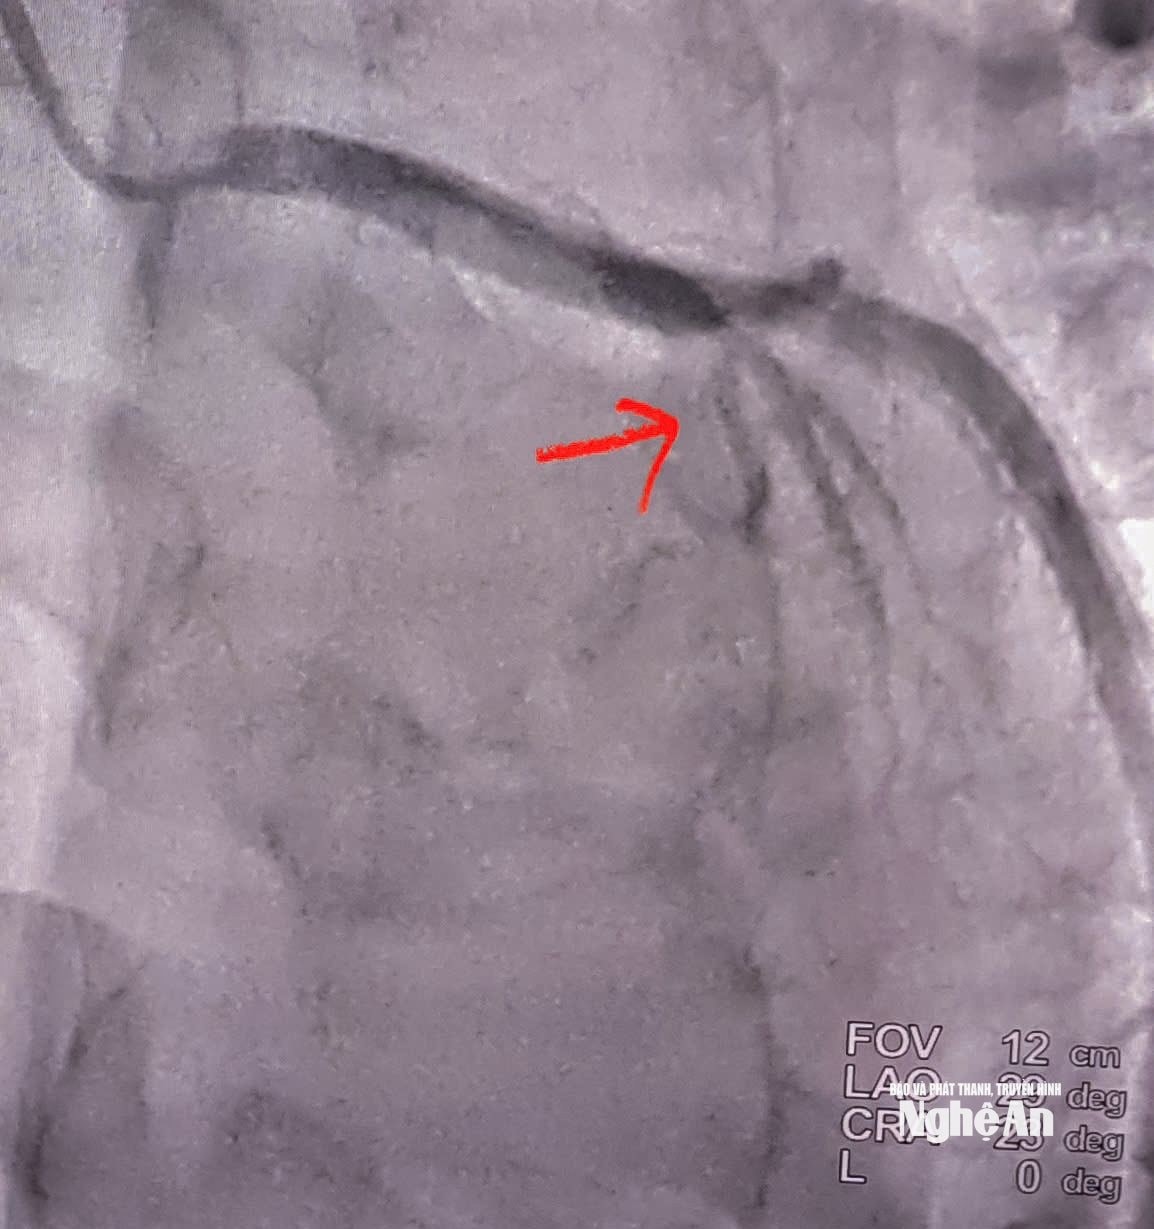

Tắc động mạch liên thất trước đoạn 2 (LADII) (Hình mũi tên đỏ). Ảnh: Bệnh viện Hữu nghị Đa khoa Nghệ An

Kết quả chụp mạch cho thấy bệnh nhân tắc hoàn toàn động mạch liên thất trước đoạn II (LAD II) - nhánh mạch vành quan trọng cung cấp máu cho phần lớn cơ tim thất trái. Ê-kíp can thiệp đã nhanh chóng tiến hành nong bóng và đặt một stent phủ thuốc tại vị trí tổn thương. Thủ thuật diễn ra thuận lợi, dòng máu được tái lập ngay sau can thiệp, cải thiện rõ rệt tình trạng thiếu máu cơ tim.